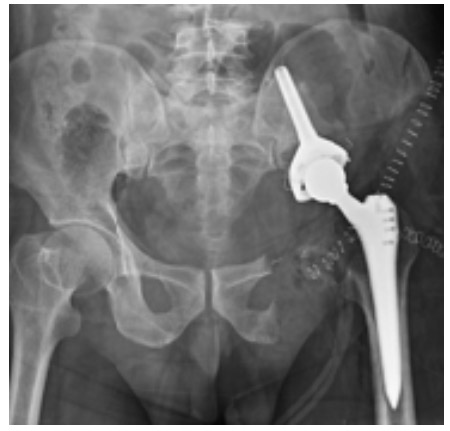

Postoperative:The X-ray shows reconstruction with a tumor prosthesis after removal of the tumorous bone and soft tissue (internal hemipelvectomy).